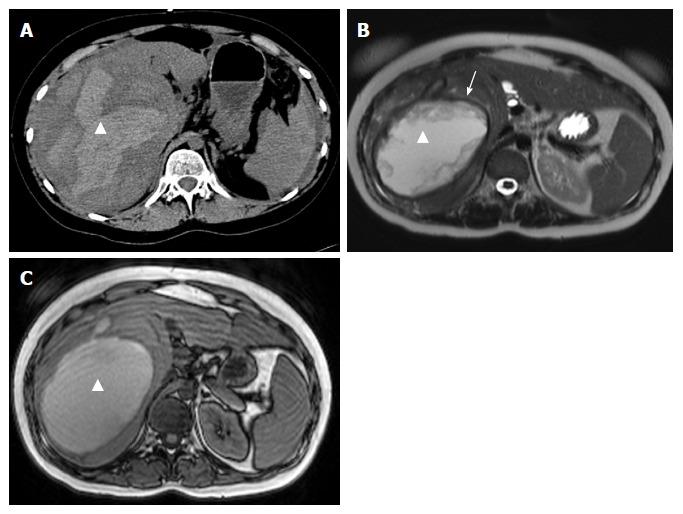

这项回顾性队列研究纳入了1999年至2016年间因HCA破裂导致大出血(Ⅱ级或Ⅲ级)并入院接受观察和/或干预的所有连续患者。HCA的诊断基于对比增强磁共振成像(MRI)的影像学表现或HCA活检或切除的病理结果。根据计算机断层扫描或MRI结果诊断出血。查阅病历以了解人口统计学特征、临床表现、肿瘤特征、初始及后续处理、短期和长期并发症以及患者和病灶随访情况。

所有患者均为女性(n = 23)。急性期治疗包括栓塞(n = 9,39.1%)、保守治疗(n = 13,56.5%)和其他干预措施(n = 1,4.3%)。干预组患者在第0至3天血红蛋白水平的中位数下降幅度明显大于最初接受保守治疗的患者(分别为0.9 mmol/L对2.4 mmol/L,P = 0.006)。共有4例患者出现严重短期并发症,包括低血容量性休克、急性肝衰竭和脓肿形成。中位随访36个月后,未接受手术治疗的患者肿瘤出现退缩,中位数从76 mm缩小至25 mm。4例患者接受了二次(择期)治疗(如肿瘤切除),以处理HCA直径>5 cm和/或未来有妊娠意愿的情况。记录到1例再出血病例(4.3%)。所有患者均未出现长期并发症(平均随访时间:36个月)。